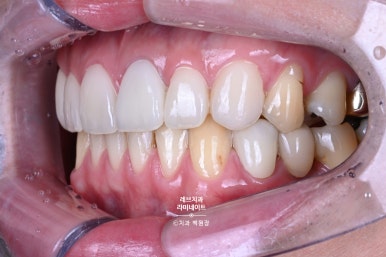

같은 사람인가? 싶을 정도로 다른 모습이라고 할 수 있죠......?

사실 여러개도 아니고, 위 앞니 단 6개만 레브네이트 엑스퍼트로 바꼈는데... 이렇게 사람 인상이 달라진답니다.

같은 사람임을 인증하기 위해서, 레브네이트 치료 받지 않은 어금니까지 보이는 사진을 첨부했습니다.

그리고 특별한 착시가 들어가 있는데요, 옆에서 보면 꽤나 송곳니가 넓어보이는 것을 확인하실 수 있을거에요. 심지어 좌우 사이즈도 좀 다르죠.

다만, 앞에서 보면 완전 대칭으로 보입니다! 앞에서 보이는 각도를 감안해서 만듦으로써 환자분이 갖고 있는 상황 내에서 최선의 결과를 내는 것.

Before & After

일단 웃었을 때 모습이 달라지셨어요.

유튜버라면 웃는 모습을 많이 보일 수 밖에 없으실텐데요,

좌우 대칭과 화사한 색상, 그리고 자연스러움까지 ... 원하시는 요구를 모두 깔끔하게 맞춰드렸습니다.

무슨 말이 필요할까요. 우측 사진이 다소 밝게 찍혔다곤 하나, 정말 리모델링을 넘어 신축 아파트가 들어선 느낌입니다!! 이제 드디어 자연스럽게 활짝 웃을 수 있다고 말씀하신 환자분. 어려운 결정이셨겠지만, 앞으로도 활짝 웃음 가득한 나날이 가득하시길 바랍니다.